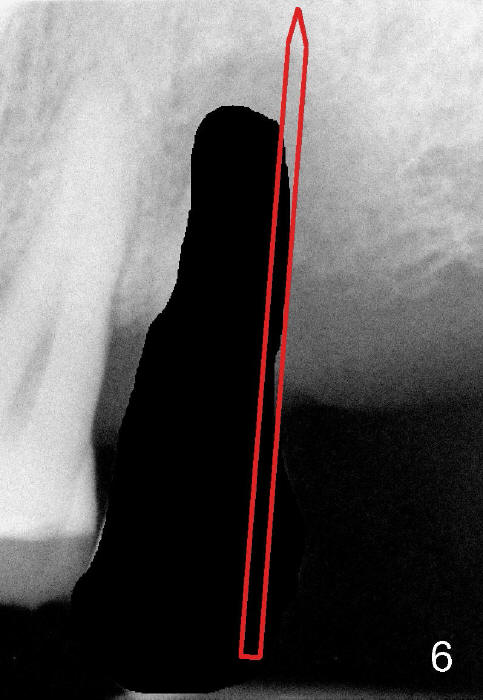

Fig.5 is an illustration showing the socket after extraction. The osteotomy is intentionally placed distally (Fig.6 arrow: pilot drill). In case the patient agrees to have ortho treatment, there will be space to correct the upper midline (7). If not, a molar crown will be fabricated. By the time a 4.5x20 mm tap is inserted (Fig.7 T), the mesial gap is visible (*). When a 6x20 mm implant is placed (Fig.8 I), bone graft is placed buccally (Fig.2, as planned) and mesially (Fig.8 red circles, as compared to Fig.1). The implant has to be as large and long as 6x20 mm to get primary stability (insertion torque 50/60 Ncm). The apex of the implant is close to the sinus floor (Fig.8 ^) or in fact the nasal floor (Fig.9 N). There appears bone growth in the mesial gap 3 months postop (Fig.10 *). There is no bone loss 2.5 years post cementation (Fig.11).